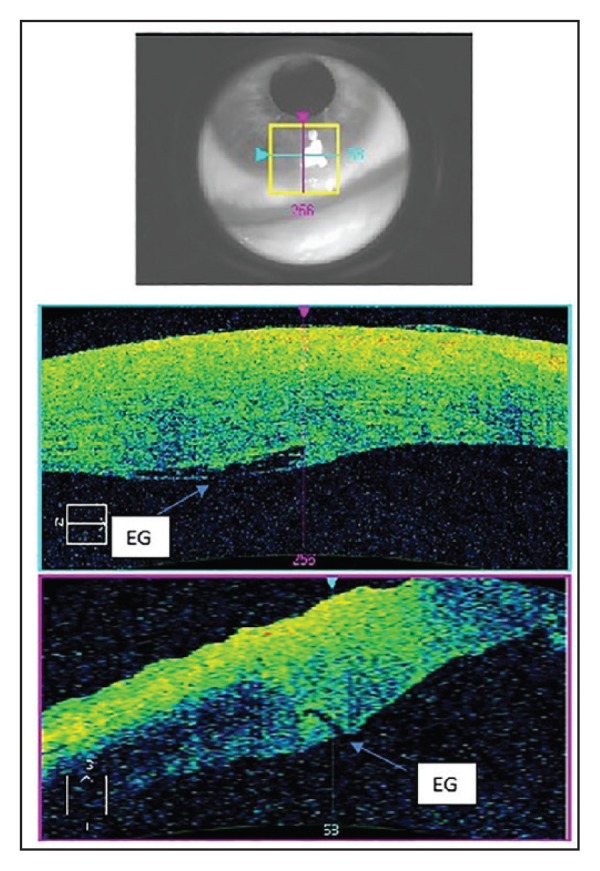

FIGURE 2.

High-resolution optical coherence tomography image showing bandage contact lens (CL) in place with corneal gaping at the endothelial side (EG) of the clear corneal incision.

FIGURE 4.

High-resolution optical coherence tomography image showing gaping at the endothelial side (EG) of the clear corneal incision.